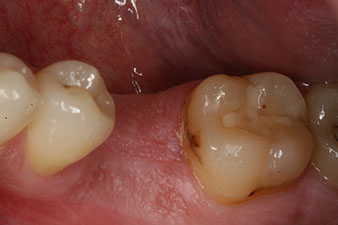

composite crown

Fig. 9: The final composite crown was cemented on a PEEK hybrid abutment in the laboratory and can be screwed in place immediately.

x-ray check

Fig. 10: The x-ray check shows the success of the osseointegration and the crown screwed in position without a gap.